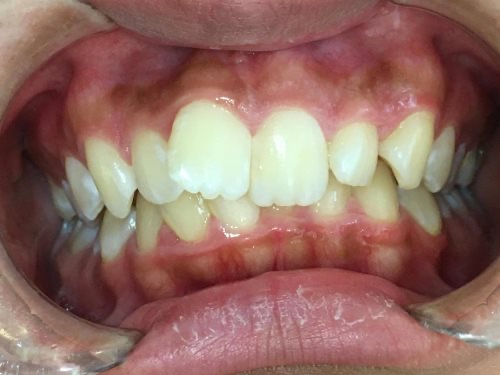

20代女性「ガタガタの歯と深い噛み合わせが気になる」取り外し式のマウスピース型矯正装置「インビザラインフル」で歯並びを整え、正しい位置で噛めるようにした症例

「ガタガタの歯並びと深い噛み合わせが気になる」とご相談いただきました。

拝見したところ、歯並びの幅が狭くスペースが不足していることにより、歯がガタガタと並んでいる「叢生(そうせい)」でした。

特に上の前歯(右上中切歯/1番)は、ねじれて前方に突き出しており、見た目が気になりました。

また、上の歯が下の歯に覆い被さっている深い噛み合わせの「過蓋咬合(かがいこうごう)」も認められ、あごの関節に負担がかかりやすくなっていました。